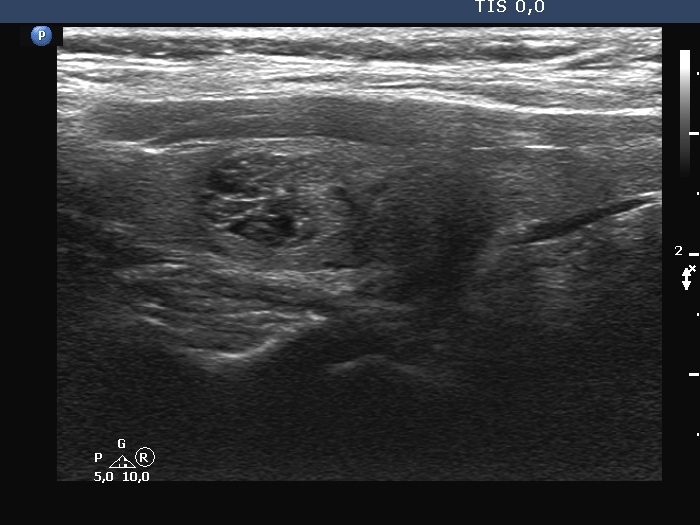

Ultrasonography. The thyroid was echonormal. There was a dominantly solid nodule in the right lobe. The lesion showed back wall cystic figures caused by posterior enhancement and nonparallel orientation. The depth of the nodule was 12 mm while the width was 10 mm.